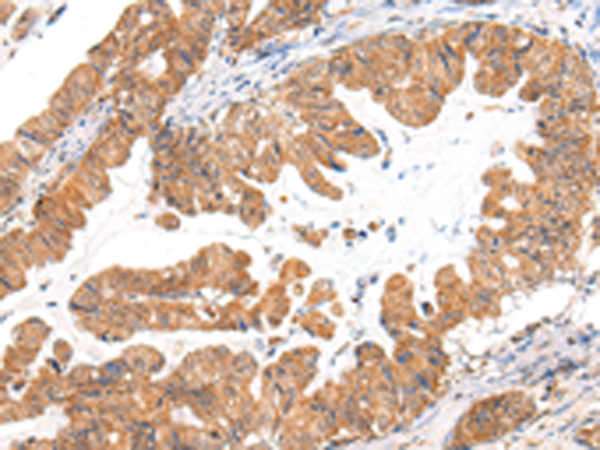

分类: 科研抗体货号: P05648别名:应用: IHC反应种属: Human, Mouse